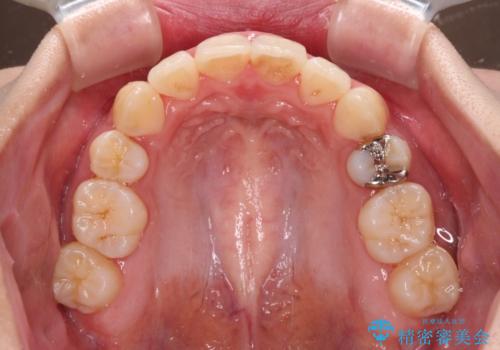

- 前歯の叢生と八重歯を気にして来院された患者様です。

叢生が強く、奥歯の咬合も左右差が大きかったため、上下左右4本を抜歯して、ワイヤー矯正を行うこととしました。

20歳前後と年齢が若かったため、非常にスムーズに歯列が整い、1年半をかけずに治療を終えることができました。